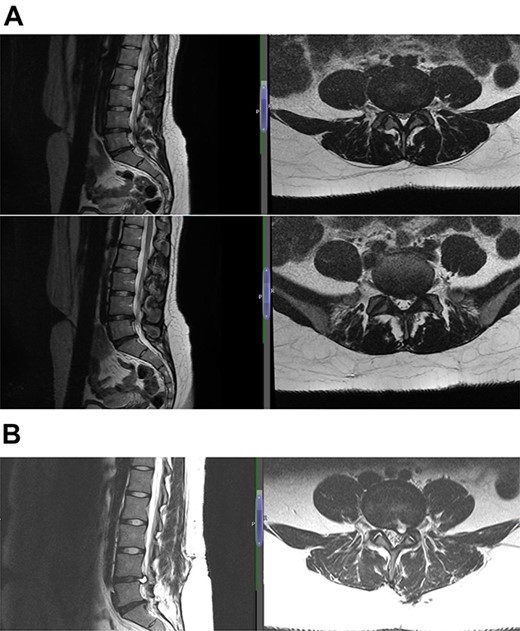

The diagnosis was reached keeping in mind the radiological and contrast scan was taken in follow-up period (Figs 1, 2a, b,3a, b and4a, b). On MRI, it was noted that the cyst was well-defined, smooth regular margins with T1 hypointense and T2 hyperintense and an evident communicating stalk with the disc while in post-gadolinium scan showed cyst wall enhancement. As discography is no longer required for reaching a diagnosis, it was not done in any of the patients.

Case 1 L5-S1 level: there is disc desiccation and slight disc height loss; there is disc protrusion (including a cystic component) with impingement to the left traversing S1 nerve root.